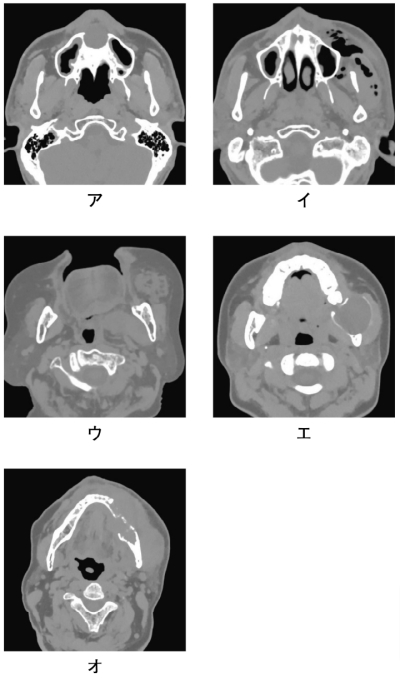

CTを別に示す。捻髪音がみられるのはどれか。1つ選べ。

a. ア

b. イ

c. ウ

d. エ

e. オ